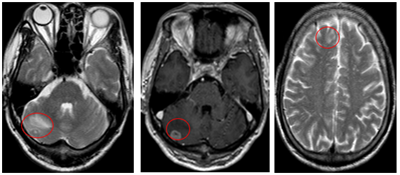

CASE LÂM SÀNG  HIỆU QUẢ CỦA OSIMERTINIB TRONG ĐIỀU TRỊ BỆNH NHÂN UNG THƯ PHỔI DI CĂN NÃO TẠI BỆNH VIỆN BẠCH MAI

Ngày đăng: 11/07/2025

Ung thư phổi là một trong những bệnh ung thư thường gặp nhất. Theo GLOBOCAN 2022, các số liệu cho thấy trên thế giới, ung thư phổi có tỉ lệ mới mắc và tỉ lệ tử vong hàng đầu. Tại Việt Nam, ung thư...